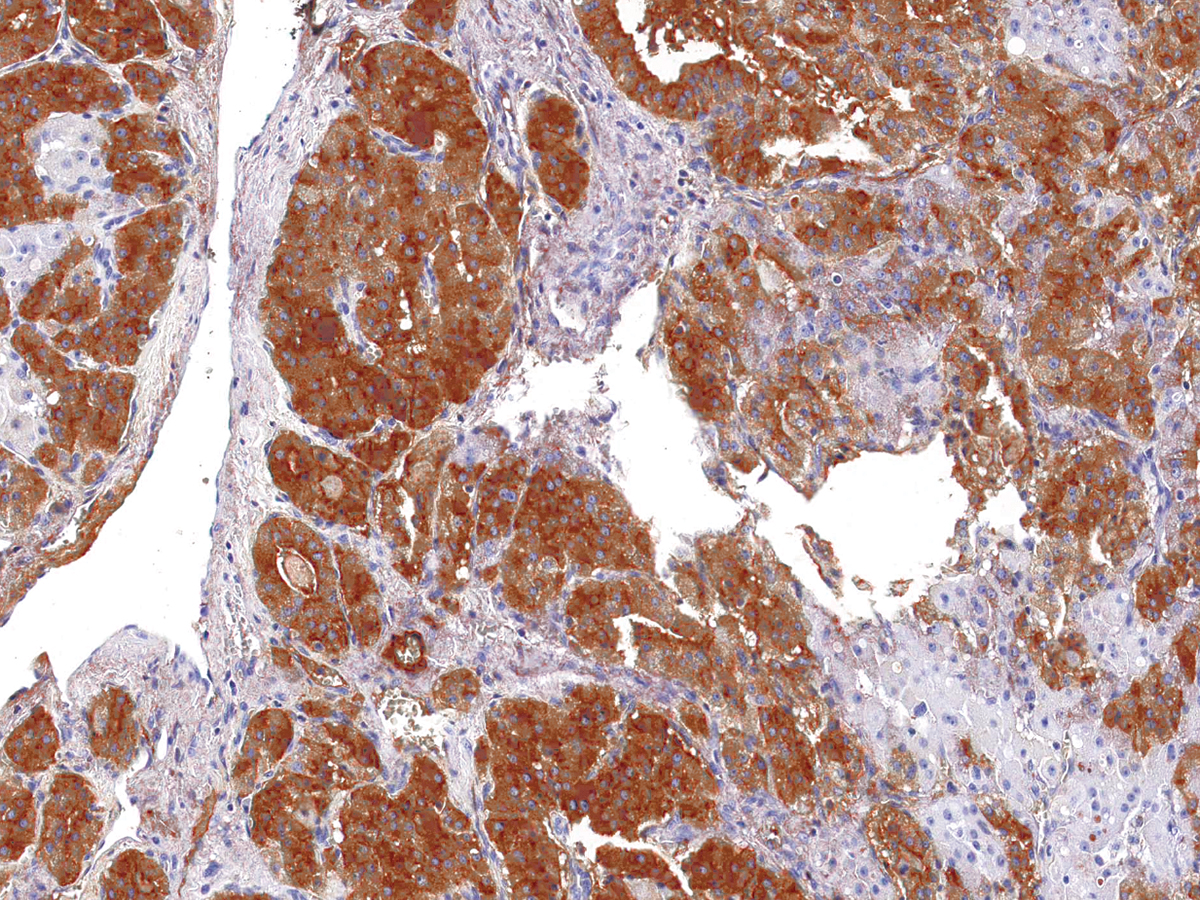

图片:

Thyroglobulin [P1054] on Thyroid Cancer